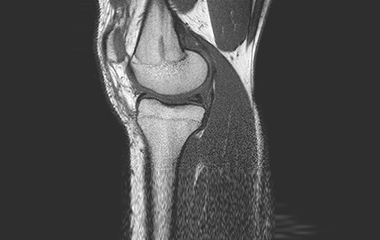

Conventional treatment of knee pain and resultant dysfunction currently does not adequately address the sources of pain due to difficulty visualizing, accessing and treating the intraosseous (bone marrow) lesion. Current clinical procedures and systems on the market only approximate the location of the lesion potentially providing a less precise clinical outcome as well as requiring fluoroscopy for localization and confirmation.

Management of early knee osteoarthritis presents a challenge for many orthopaedic surgeons and patients. Etiology from many of these patients originates from bone marrow lesions (subchondral edema) and if left untreated could lead to progressive pain, progression of arthritis, and subsequent need for knee arthroplasty(1).

The PanPlasty Instrument System is uniquely designed to precisely target and delivery biomaterials to ensure precise treatment of intraosseous lesions potentially lessening/alleviating patient pain and delaying the need for more complex and invasive arthroplasty surgical procedures.